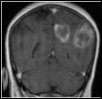

Décidément on ne peut plus ignorer la génétique y compris (voire surtout) au moment de prescrire un traitement. C’est ce qui vient de constater une équipe internationale de chercheurs avec un groupe des patients atteints d’un gliome malin ou glioblastome, une tumeur maligne du cerveau provoquée par une multiplication anarchique des cellules gliales. Cette anarchie se traduit dans le nombre des cellules mais aussi dans leur structure. Lorsque les patients sont traités par la temozolomide (Temodal®, Schering-Plough) on observe chez certains d’entre eux une inhibition du développement tumoral et pas d’inhibition chez autres. La raison vient d’être découverte dans le noyau des cellules.